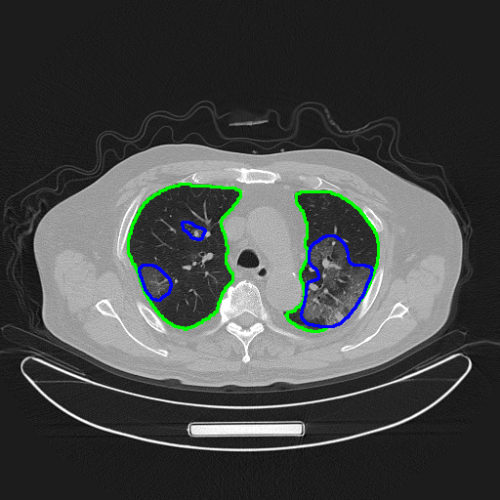

AI對(duì)病人肺部和新冠肺炎病灶做了精確的自動(dòng)分割

“騰訊覓影”對(duì)新冠肺炎影像識(shí)別模型也做了針對(duì)性的優(yōu)化。通過肺炎病灶區(qū)域的精確分割,提供定量分析,以方便影像醫(yī)生在短時(shí)間內(nèi)對(duì)患者病情的嚴(yán)重程度及發(fā)展過程做出準(zhǔn)確評(píng)判。下一步還將提供病例隨訪等功能,方便醫(yī)生快速比對(duì)患者病情,評(píng)估治療效果。